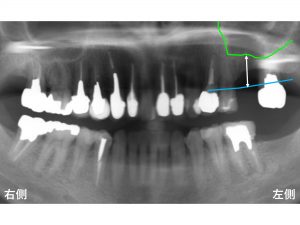

以下が初診時です。

上顎左側奥から2番目が欠損しています。

骨が吸収しているのです。

わかりやすいように骨吸収の状態を線でかいて見ます。

以下の青線が骨吸収する前の元々の骨の位置です。